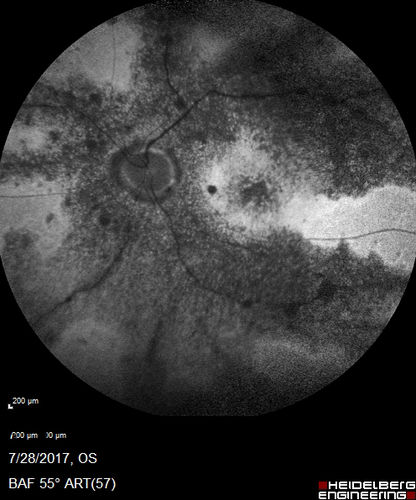

Pigmented Paravenous Retinochoroidal Atrophy - Left Eye

70 year old woman lost vision OS 20 years ago.